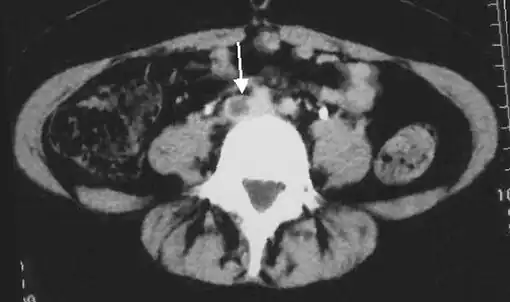

Thrombolysis is the injection of an enzyme into the veins to dissolve blood clots, and while this treatment has been proven effective against the life-threatening emergency clots of stroke and heart attacks, randomized controlled trials[139][140][141] have not established a net benefit in those with acute proximal DVT.[5][142] Drawbacks of catheter-directed thrombolysis (the preferred method of administering the clot-busting enzyme[5]) include a risk of bleeding, complexity,[lower-alpha 12] and the cost of the procedure.[125] Although, while anticoagulation is the preferred treatment for DVT,[125] thrombolysis is a treatment option for those with the severe DVT form of phlegmasia cerula dorens (bottom left image) and in some younger patients with DVT affecting the iliac and common femoral veins.[12] Of note, a variety of contraindications to thrombolysis exist.[125] In 2020, NICE kept their 2012 recommendations that catheter-directed thrombolysis should be considered in those with iliofemoral DVT who have "symptoms lasting less than 14 days, good functional status, a life expectancy of 1 year or more, and a low risk of bleeding."[138]

A mechanical thrombectomy device can remove DVT clots, particularly in acute iliofemoral DVT (DVT of the major veins in the pelvis), but there is limited data on its efficacy. It is usually combined with thrombolysis, and sometimes temporary IVC filters are placed to protect against PE during the procedure.[143] Catheter-directed thrombolysis with thrombectomy[141] against iliofemoral DVT has been associated with a reduction in the severity of post-thrombotic syndrome at an estimated cost-effectiveness ratio of about $138,000[lower-alpha 13] per gained QALY.[144][145] Phlegmasia cerulea dolens might be treated with catheter-directed thrombolysis and/or thrombectomy.[19][143]